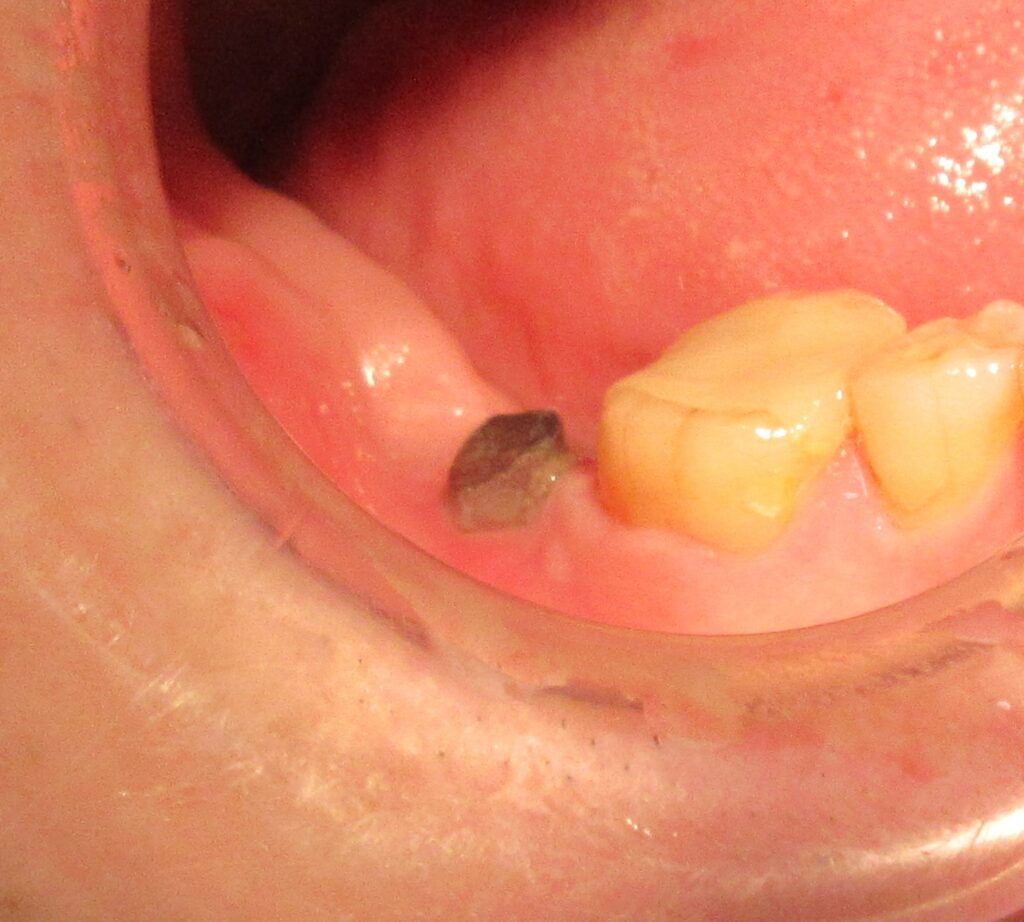

今回の患者様はインプラント植立を希望され、右下7番目の植立が決まりました。

まずは歯茎から骨の部分までを穴開けパンチの要領で穴を開けていきます。

くりぬいた部分の歯肉を取り除き、次は骨に穴を開けていきます。